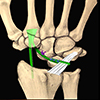

The FCR over-capitate tenodesis was performed using a combined volar and dorsal approach, following the method originally described by Garcia-Elias and later refined by Luchetti et al. [10, 13, 14]. A distally based slip of the flexor carpi radialis tendon was harvested volarly and routed from the volar aspect of the wrist to the dorsal side through the midcarpal interval. After scaphoid excision and radiocarpal realignment, the tendon was passed over the neck of the capitate and looped around the radiotriquetral ligament to create a stabilizing sling. The dorsal limb was secured with non-absorbable sutures, and a dorsal capsular flap was advanced to reinforce the construct. This technique was selected in patients with preserved radiolunate and capitolunate cartilage who preferred a motion-preserving reconstruction.

Figure 1 Scaphoidectomy and midcarpal tenodesis with the FCR tendon slip. The tendon is fixed at the neck of the capitate, passing around the Radiotriquetral ligament, and then sutured to itself (schematic). Source: Dr. Emmanouil Apergis. |